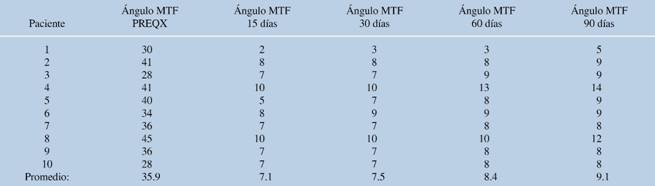

Se obtuvo un total de 14 pacientes; cuatro fueron excluidos: dos con el diagnóstico de artritis reumatoide y otros dos por contar con el diagnóstico de hallux valgus leve según la clasificación de Coughlin y Mann. De la muestra estudiada, en 10 pacientes a quienes se les realizó el diagnóstico de hallux valgus moderado a severo, se encontró una distribución de edad de 36 a 78 años, con una media de 52.8 años; predominó el sexo femenino, con 100%. Se aplicó la escala AOFAS a todas las pacientes, tal como se describió previamente y se muestra en la Tabla 1.

Tabla 1: Resultados de la valoración de la escala AOFAS de acuerdo al tiempo de evolución.

PREQX = previo al tratamiento quirúrgico.

La corrección media del ángulo intermetatarsiano fue de 8.8 grados y la del ángulo metatarsofalángico, de 9.12 grados (inicial de 15 y 36.87 grados, respectivamente) (Tablas 2 y 3). Se presentó una complicación transoperatoria, con fractura diafisaria del segundo metatarsiano que se resolvió en el mismo evento mediante fijación con clavo Kirschner 1.6 mm. El análisis estadístico mostró una correlación inversamente proporcional de la corrección del ángulo intermetatarsiano y el puntaje de la escala AOFAS (p = 0.02).